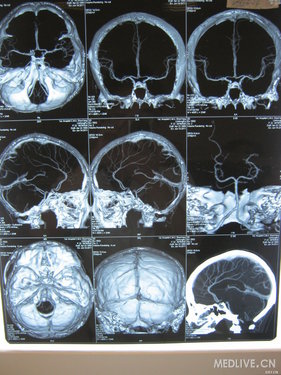

病史特点:22岁年轻女性,以“头痛伴右眼视力下降,左侧肢体活动不灵2天”为主诉入院,2天前在美容院行额头填充物--玻尿酸取出手术时突然起病,自觉全身发热不适,呼吸急促,并出现抽搐发作:双眼向右侧凝视,双上肢屈曲,右腿伸直,左腿屈曲,呼之不应,无尿失禁及舌咬伤,5-6分钟缓解。抽搐后1小时患者开始出现右眼视物不清,右侧后枕部严重疼痛伴恶心呕吐,且左侧肢体麻木,急送医院,行头CT无异常,但出现左侧肢体不能活动,且频繁呕吐,转我院就诊,行头MRI+DWI检查提示:右侧大脑半球,侧脑室旁,半卵圆中心及左侧额叶皮呈及皮呈下多发长T2信号,DWI高信号。

检查:头MRI+DWI:描述如上,急性脑栓塞?

头CTA:左侧大脑中动脉M2以远分支叫对侧稍稀疏。

下面是患者的头MRI检查图像,请各位战友讨论下本病例,挤压右眼眉处粉瘤及玻尿酸取出术与患者发病有无关系,若有是怎样的机制?若无,本次发病病因何在?

病例特点:青年女性,发病时有癫痫发作,其后出现左侧肢体运动障碍,并右眼视力下降。脑MR可见颅内广泛病变,以左侧脑白质为主。